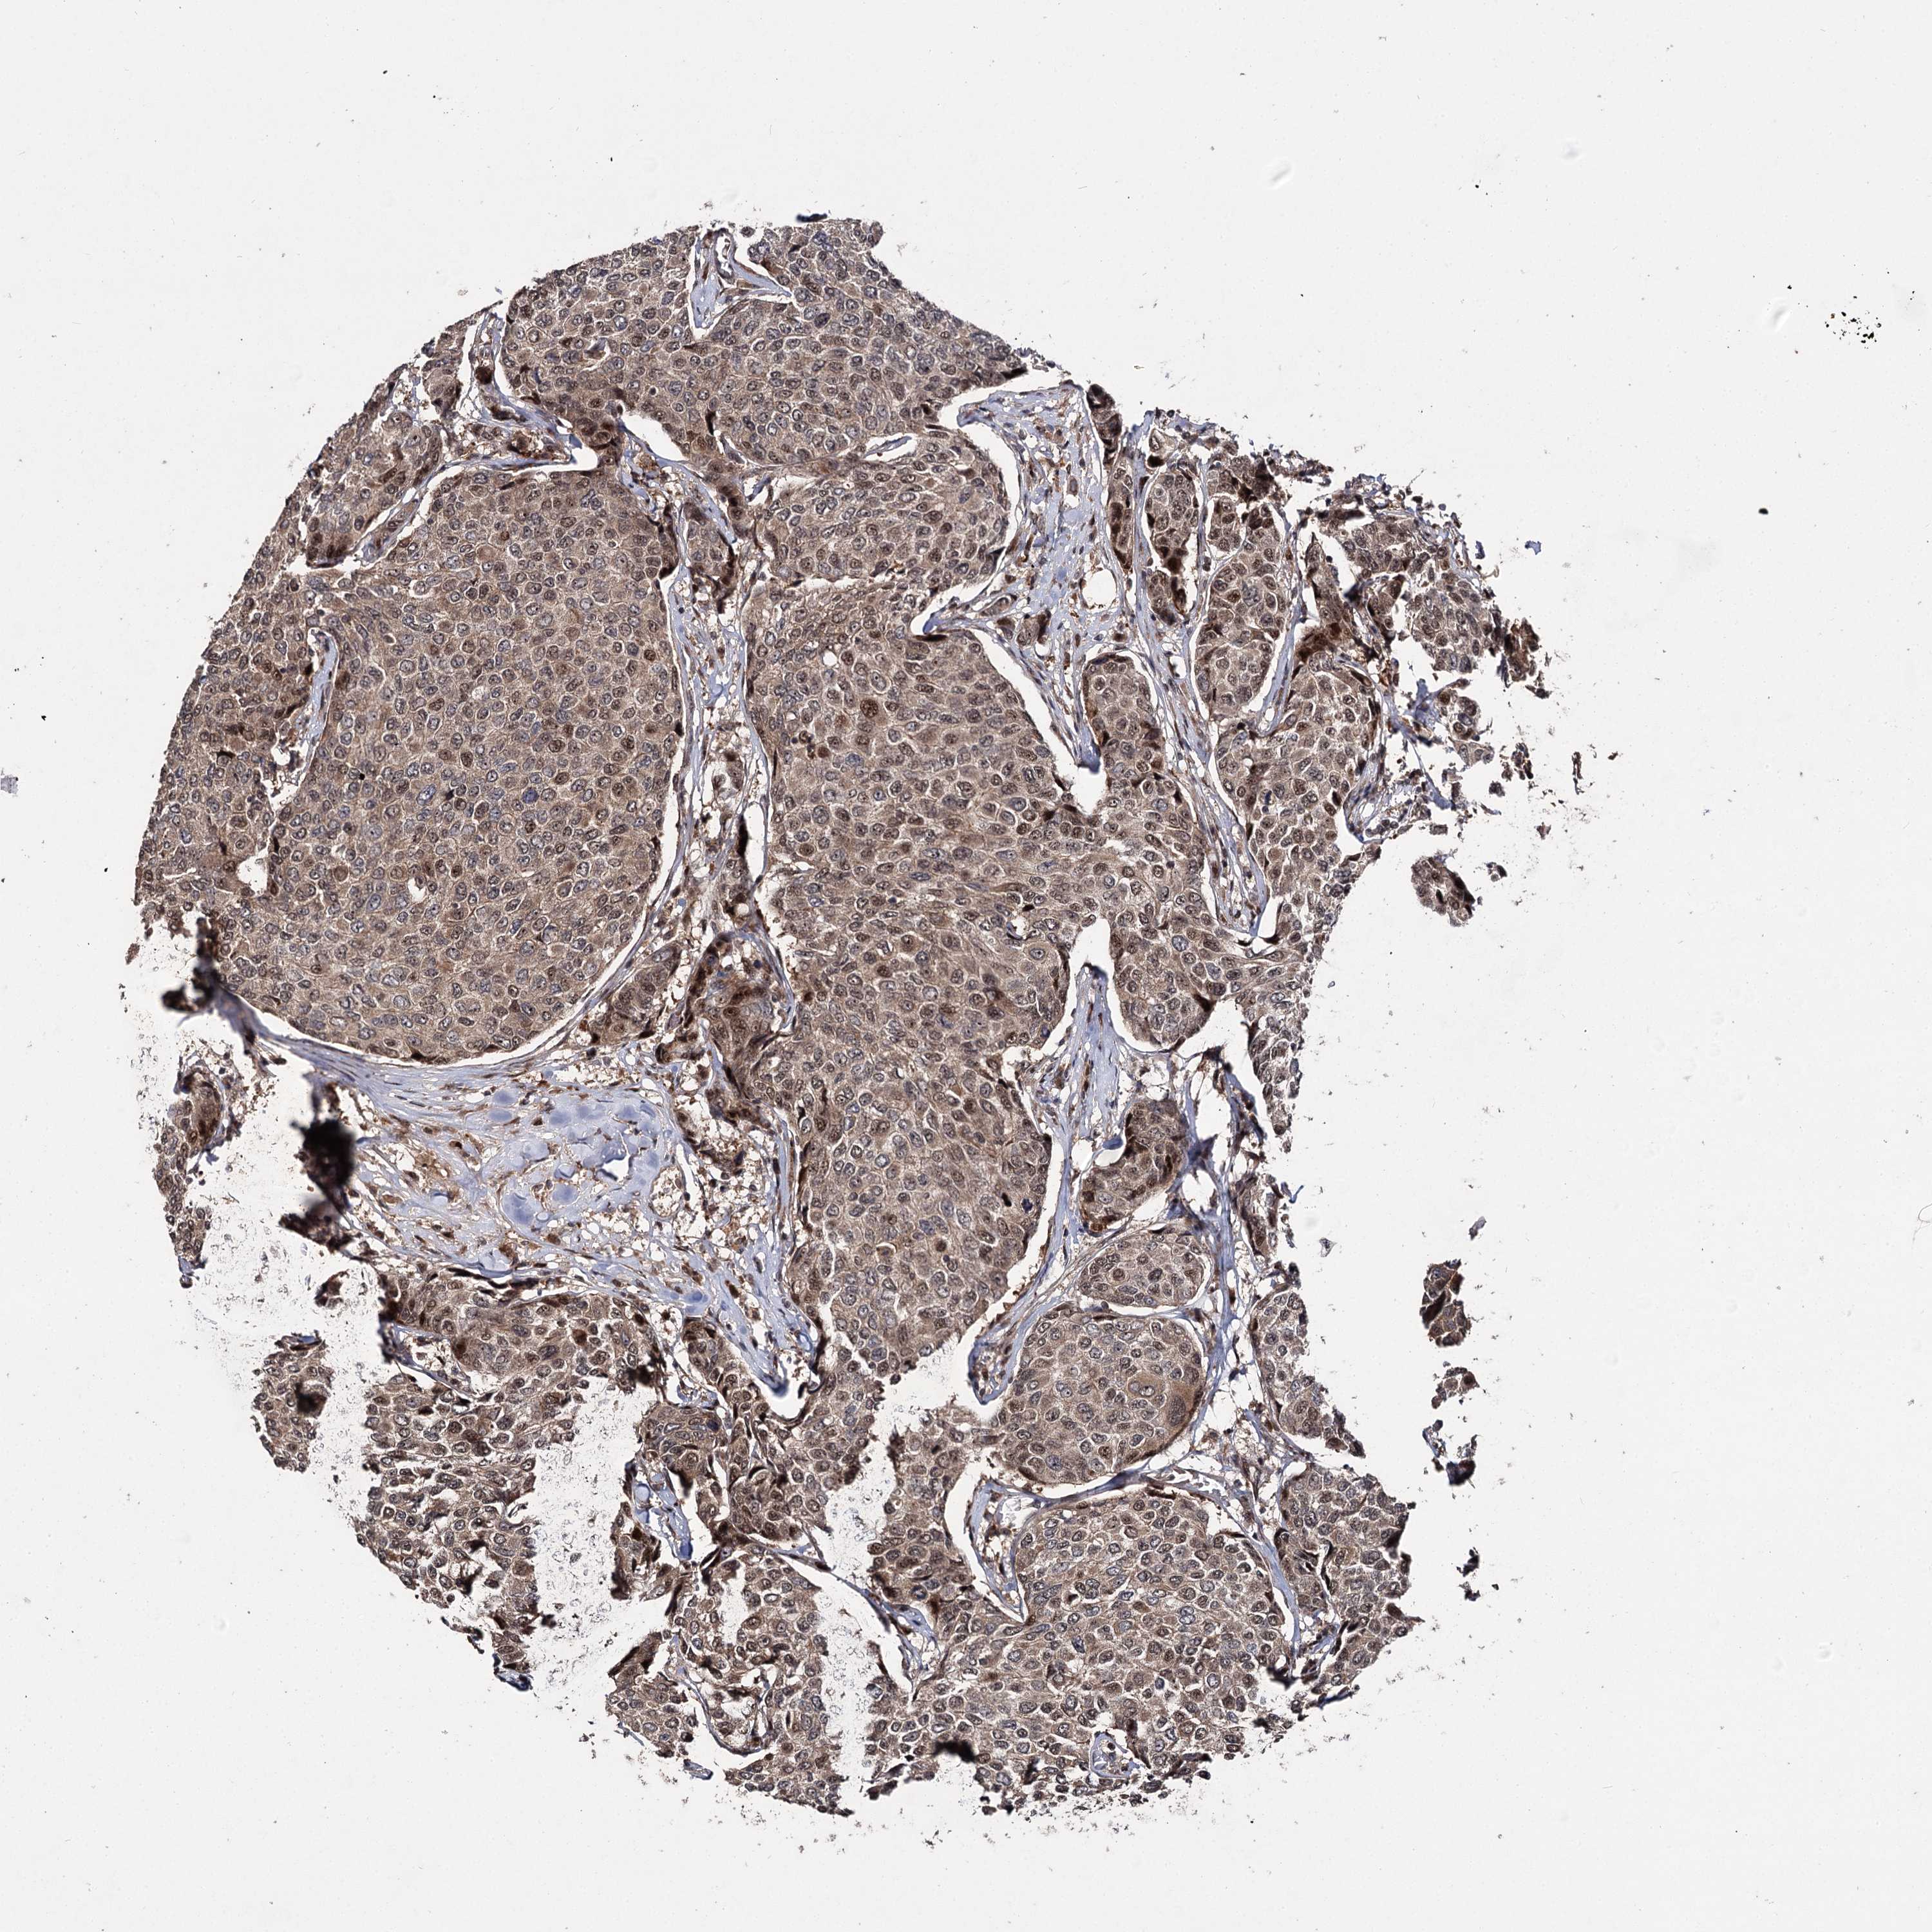

BRCA TCGA BRCA VALIDATION PROTEIN EXPRESSION

ANTIBODIES

AND

VALIDATION